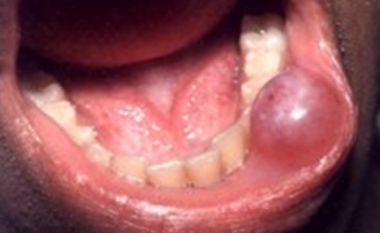

Een van de meest voorkomende afwijkingen is het opgezwollen speekselkliertje in de onderlip, de mucocoele. De mucocoele schemert vaak een beetje blauw. Bij doorprikken komt er wat taai ingedikt speeksel uit. De behandeling bestaat uit een chirurgische verwijdering. Deze kan onder plaatselijke verdoving plaatsvinden.